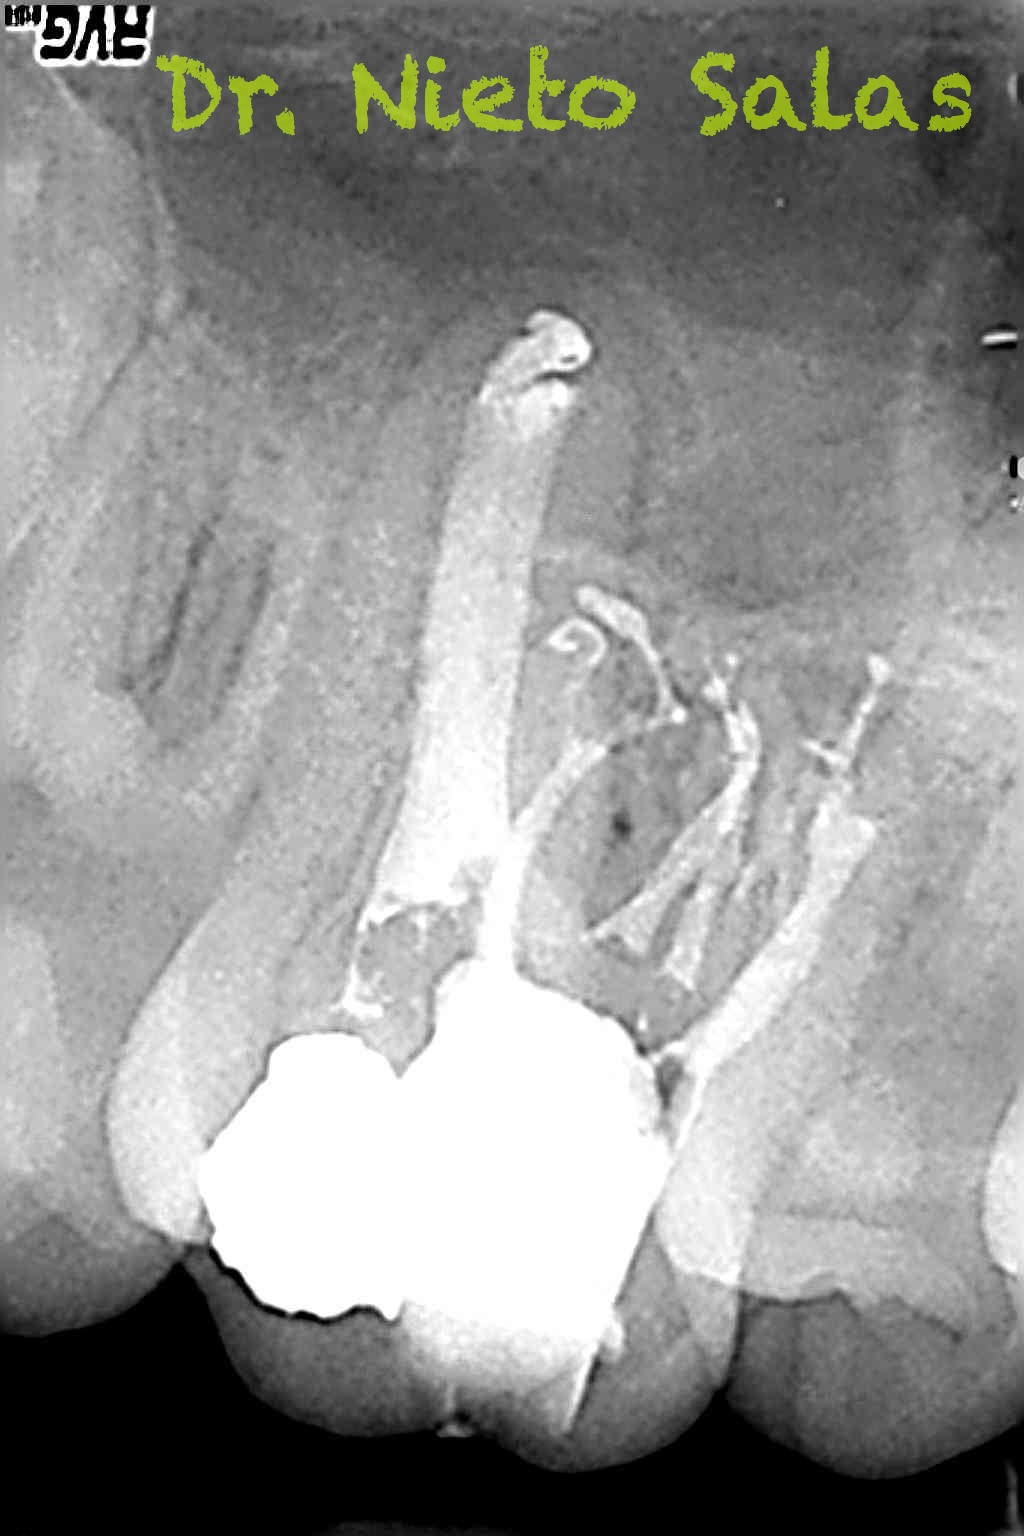

Os presento unos casos de varios molares superiores, con tres conductos mesiovestibulares con un foramen o con dos.

Una vez que tenemos medidas, obturamos los conductos: